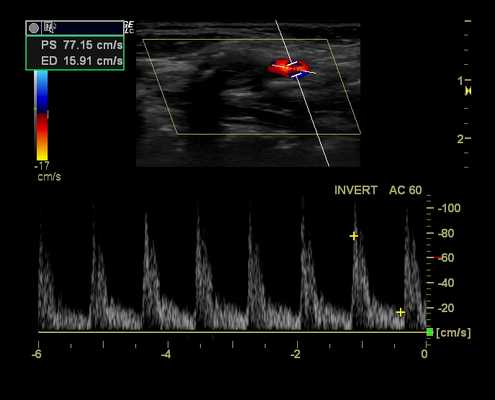

Наружная сонная артерия (НСА). НCA обеспечивает кровоснабжение сосудистого русла с высоким сопротивлением - лицо и кожу головы. Спектральные допплеровские характеристики будут демонстрировать резкий систолический подъем вверх, быстрое замедление с заметной дикротической выемкой. Компонент диастолического потока в нормальном сосуде будет уменьшаться, отсутствовать или полностью изменяться. Звуковой сигнал будет коротким и резким, с высоким тоном в систоле и слабым сигналом потока или без него в диастоле.